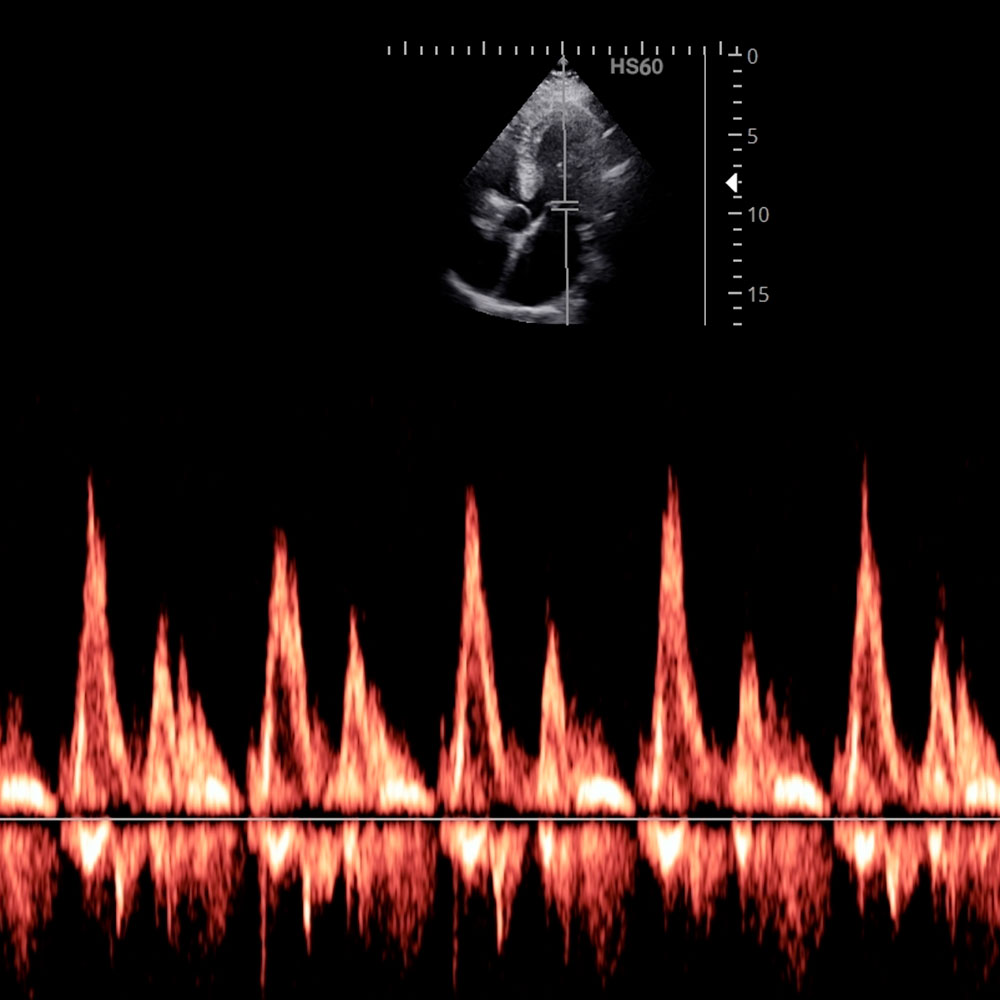

Sonographie mit Dopplermessungen

Doppleruntersuchung von Blutgefäßen

Mit der Dopplersonographie kann der Blutfluß in Venen und Arterien beurteilt werden. Dies dient der Erkennung von Engstellen in Arterien z.B. an der Halsschlagader oder den Arterien an den Beinen bei Durchblutungsstörungen. Auch zur Erkennung von Thrombosen kann das Verfahren eingesetzt werden.